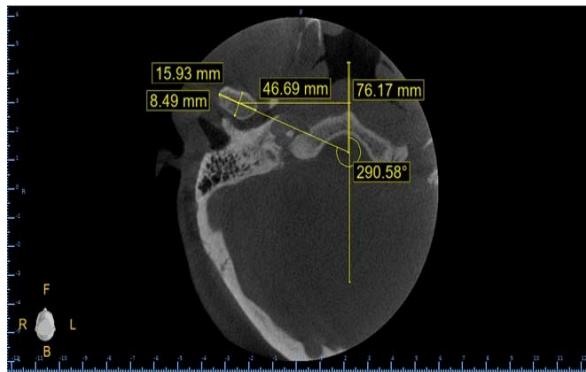

Cláudio Roberto Tavares Pereira Filho et al. Influence of Tooth Loss and Malocclusions on Condylar Position: Analysis by Cone Beam Computed Tomography